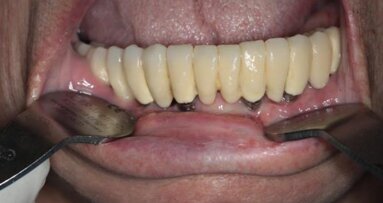

67-letnia pacjentka zgłosiła się do gabinetu stomatologicznego w celu konsultacji w sprawie leczenia implantologicznego. W wywiadzie zgłaszała pewne ...